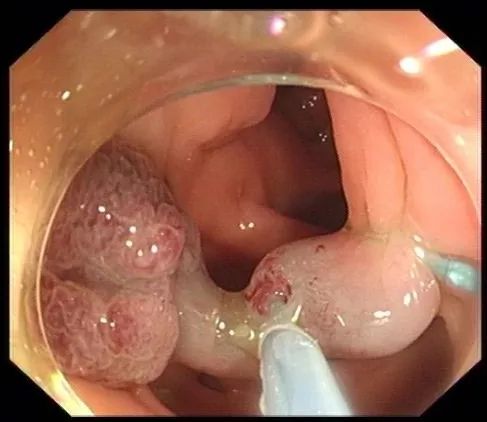

2. 广基大息肉:

直径<2cm的:可采用内镜黏膜切除术(EMR)治疗,即先在病变黏膜下注射生理盐水抬起病变,再用圈套器电切除息肉。

图片

对于直径>2cm的广基大息肉和平坦型病变,即大肠侧向发育型肿瘤(LST):如果选择EMR治疗,只能通过分块切除的方法,但该方法复发率较高,且不能进行准确的病理检查;故优先推荐采用内镜黏膜下剥离术(ESD),大块、完整地切除病变,并进行完整、准确的病例评估。